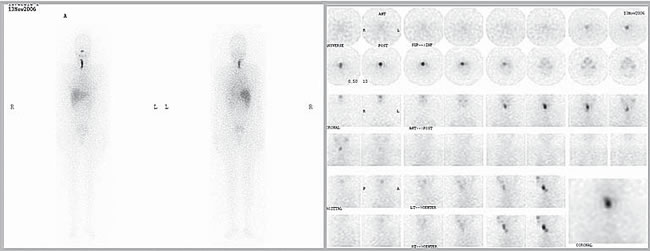

Se inició tratamiento con L-tiroxina (Eutirox®) en dosis ascendentes hasta llegar a 150 mcg/d (TSH: 0,06 uUI/mL). Al completar un año de operada, la ecografía cervical fue totalmente negativa, pero la Tg estimulada fue 8,7 ng/mL (TSH: 64 uUI/mL) con negatividad de los Ac anti Tg. Después de una segunda dosis de 100 mCi de I131, el rastreo sistémico sólo mostró un leve aumento en la captación de I131 en línea media baja, en situación retro esternal (Figura 2). El hallazgo descrito correspondía a captación mediastínica. En el control a los 18 meses, la Tg (sin estímulo) era indetectable (< 0,5 ng/mL), persistiendo la negatividad de los Ac anti Tg. Al completar el segundo año de seguimiento, la ecografía cervical no mostró ningún hallazgo patológico. Dado el antecedente de captación cervical baja, se solicitó un TAC cervical y torácico que mostró un lecho tiroideo libre y ausencia de adenopatías; en el mediastino superior, se describe una imagen triangular en el espacio prevascular, que se interpretó como persistencia del timo (Figura 3).

Figura 2. Exploración sistémica post segunda dosis de I131 (100 mCi), con captación intratorácica. La fl echa señala la imagen del timo.

Figura 3. Tomografía computada de tórax mostrando la presencia de timo.

Este caso ejemplifica como, en situaciones como la descrita, se está proclive a interpretar la captación cervical anterior baja del isótopo como parte de la enfermedad tumoral, más aún si el genio biológico del tumor es agresivo, como sucedió en nuestra paciente, y asociado a Tg positiva (8 ng/mL). Sin embargo, en el control efectuado a los dos años de la cirugía, y habiendo recibido dos dosis de yodo radioactivo, la ausencia de hallazgos ecográficos, y la negatividad de la tiroglobulina, pero con persistencia de la captación mediastínica alta de I131, hizo plantear una causa espuria de esa captación, siendo la primera de ellas la persistencia del timo. Las imágenes del TAC confirman esa hipótesis diagnóstica (Figura 3).